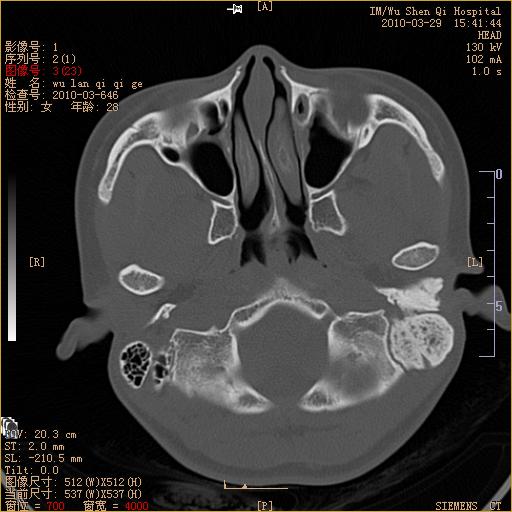

标题: CT25398:女,左耳流脓两年余,带有异物 [打印本页]

标题: CT25398:女,左耳流脓两年余,带有异物

左侧中耳乳突炎,不排除胆脂瘤形成。

左侧中耳乳突炎,胆脂瘤形成。

左侧中耳乳突炎,不排除胆脂瘤形成

1)左侧慢性中耳乳突炎并肉芽肿(或胆脂瘤)形成。2)考虑左侧颞骨慢性炎症伴骨质增生硬化,不排除骨纤。